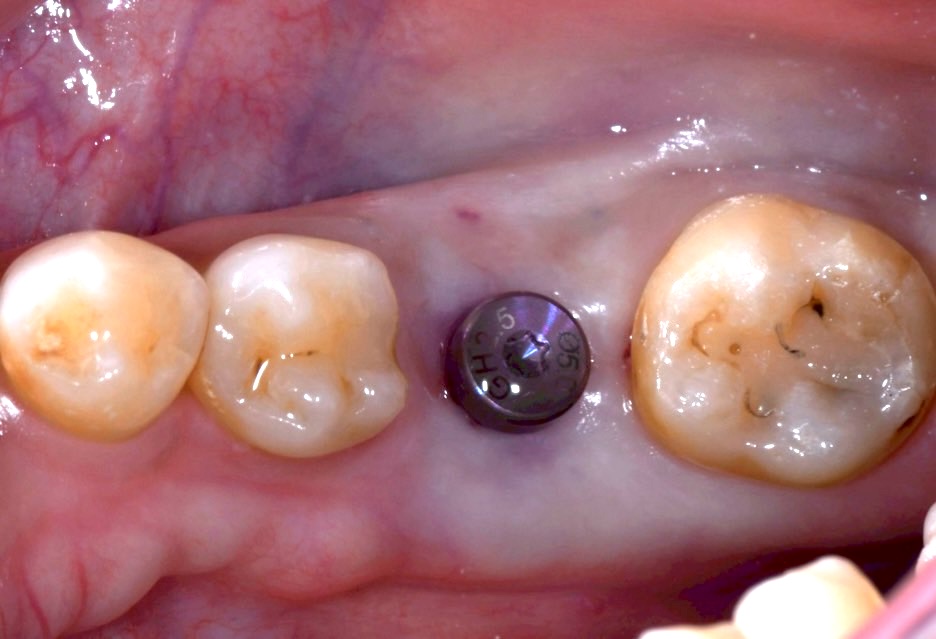

正式假牙

量身打造自然、美觀的正式假牙。

完成治療

待牙齦與骨頭癒合後,透過數位印模製作自然、美觀的正式假牙,恢復良好咀嚼與美麗笑容。